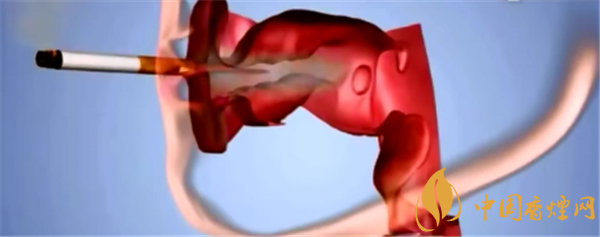

第一,烟雾中含有超过50种强致癌物质。它们是能诱导基因突变的化合物,不同化合物可能会造成不同的基因突变。

第二,烟雾对肺的损伤很大,会导致组织损伤严重会使细胞坏死。修复的主要办法就是诱导有分化潜能的细胞生长分裂,来产生新细胞来弥补受损组织。长期吸烟就是反复的“损伤-修复-损伤-修复”的过程。但不是所有的损伤都能够得到有效修复,也不是所有的修复都准确无误,任何一次生长分裂都有产生新突变的可能性,也会积累大量的基因突变。#p#副标题#e#